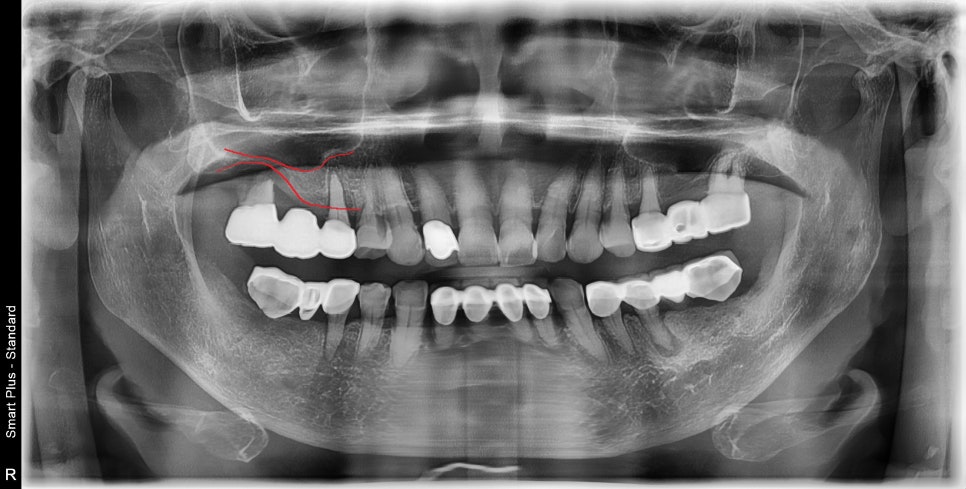

엑스레이를 찍어보니 뿌리쪽 염증으로 인해

골의 양이 충분치 않았고,

오래전에 임플란트가 보편화되기 전 시절에 하신듯싶은

최후방 어금니를 캔틸레버라고 하는

치아에 무리를 주는 보철물을 하고 계셨습니다.

일단 한쪽부터 하기로 했습니다.

어르신께서 맨 끝에 어금니까지는 필요 없을 것 같다며,

앞쪽 2개씩만 만들고 싶다고 하셨습니다.

부족한 치조골은 상악동 거상술을 통해 부족한 뼈를 만들어 주었습니다.